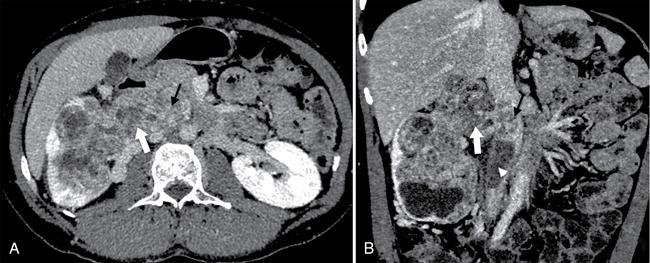

• Nonenhancing filling defect in renal vein with luminal expansion in acute thrombosis (Fig. 10.18.1.8A and B).

Fig. 10.18.1.8 (A) A case of left renal vein thrombosis as hypodense filling defect (arrows) in left renal vein causing total occlusion. (B) Another case of left renal vein thrombosis (block arrow) is also shown. Also note thrombosis of segmental renal vein (arrowhead).